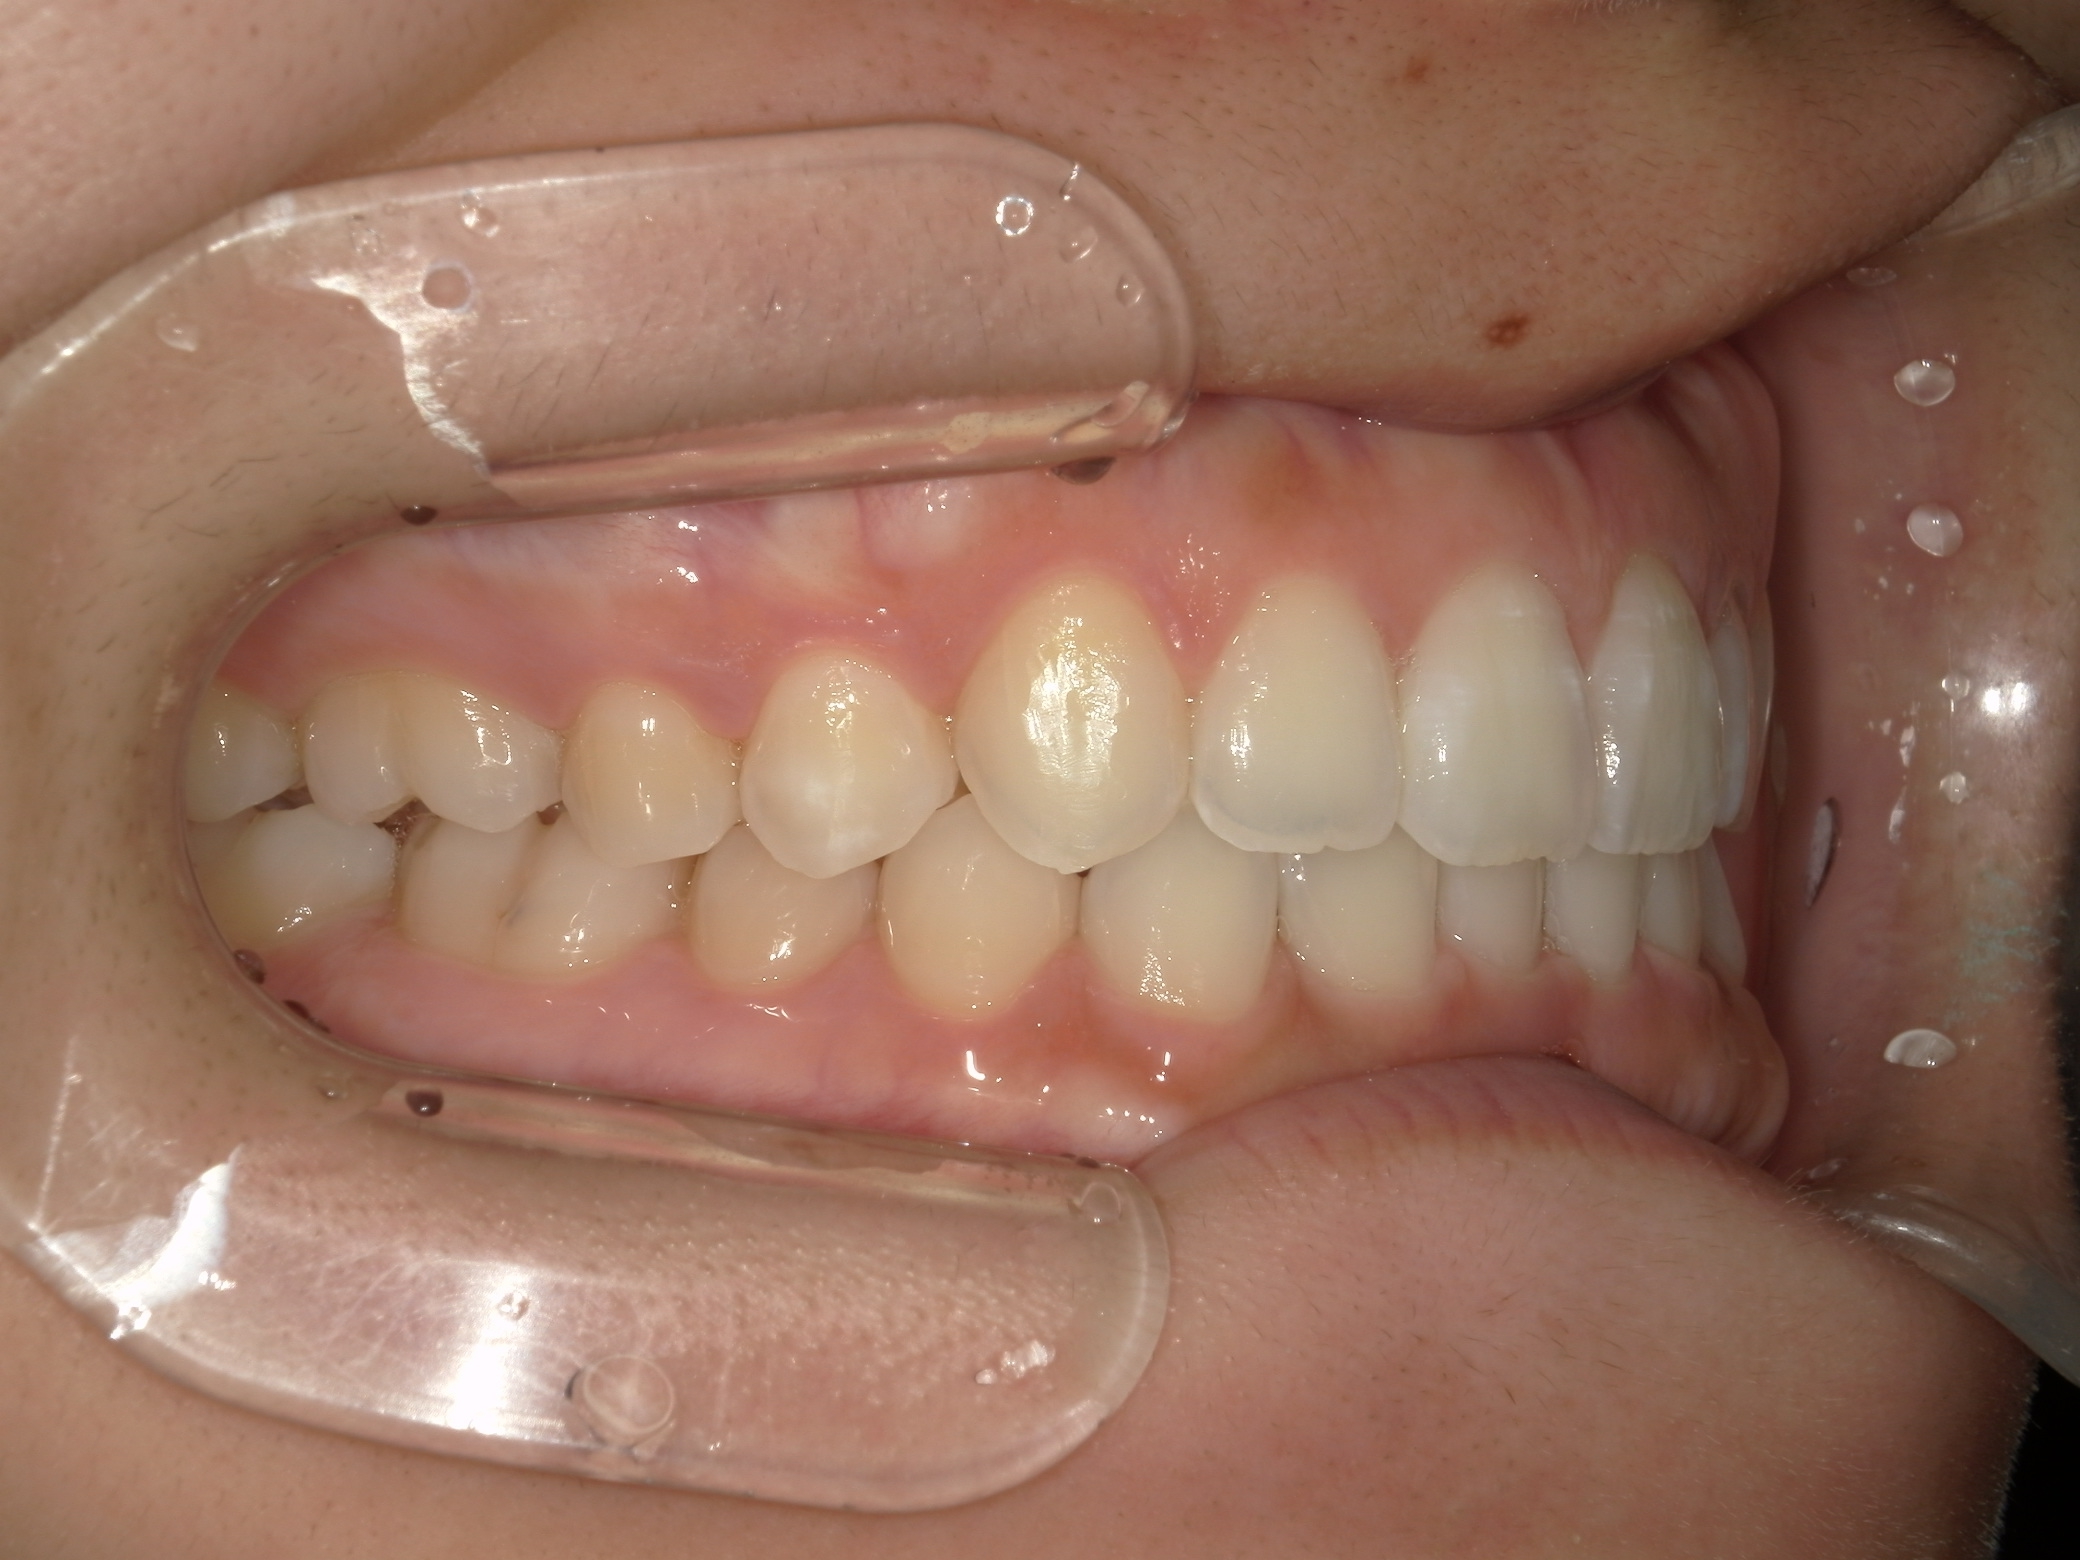

治療後の横からの歯並び

-